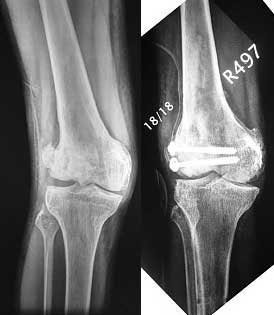

This 20 year old patient sustained a fracture in the lower end of the femur, one and a half years ago, with a compound wound over the fracture area. Notes at that time mention a compound fracture dislocation, with a loss of part of the lateral condyle. This was treated by debridement, and external fixation. After two weeks, the lateral condyle (coronal fracture) was fixed by a screw and k wire in an AP direction.

At present, he has a valgus deformity of the knee, with 0-45 degrees of movt. The knee is stable to examination, could not be corrected to neutral from the existing valgus, and despite the deformity he is walking on it, albeit with pain and some difficulty.

This was fixed temporarily, bone grafted with tricortical struts, and fixed by two cancellous screws. The fragment was not large enough to afford any fixation to a plate or such implant, and the screws held it compressed well to the rest of the distal femur.

Post-op - limb is well aligned, rom 0-30, but I am not pushing that right now, for the next two or three weeks.

Pictures attached.